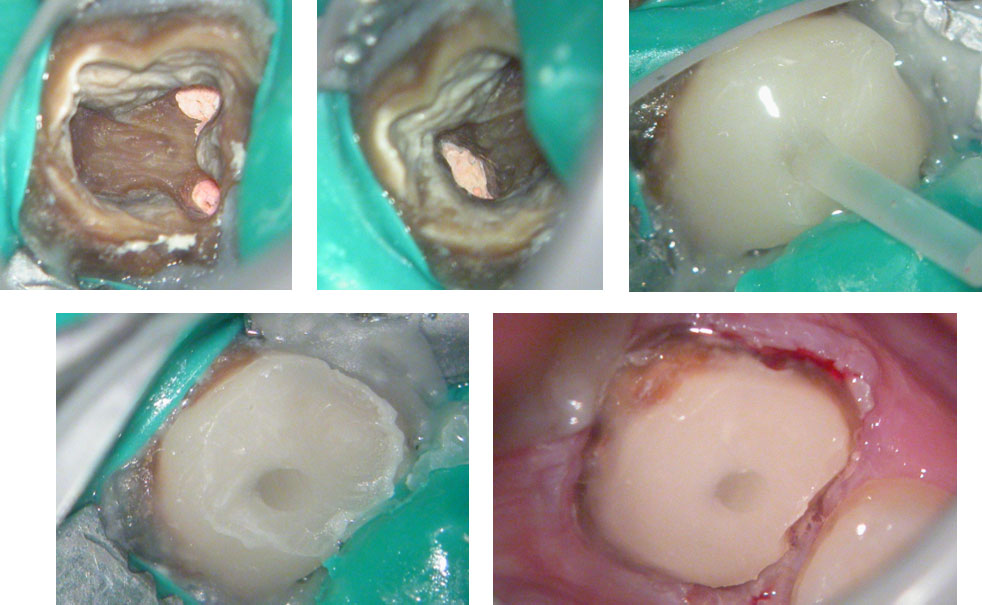

Clinical Case

PRE-OP

Distal sub-gingival caries

Distal wall built-up temporarily with glass Ionomer

Large pulp stone (red arrows) seen

Removal of pulp stone reveals an untreated distal canal which was (surprisingly) vital and hyperaemic

POST-OP

PRE-OP & POST-OP